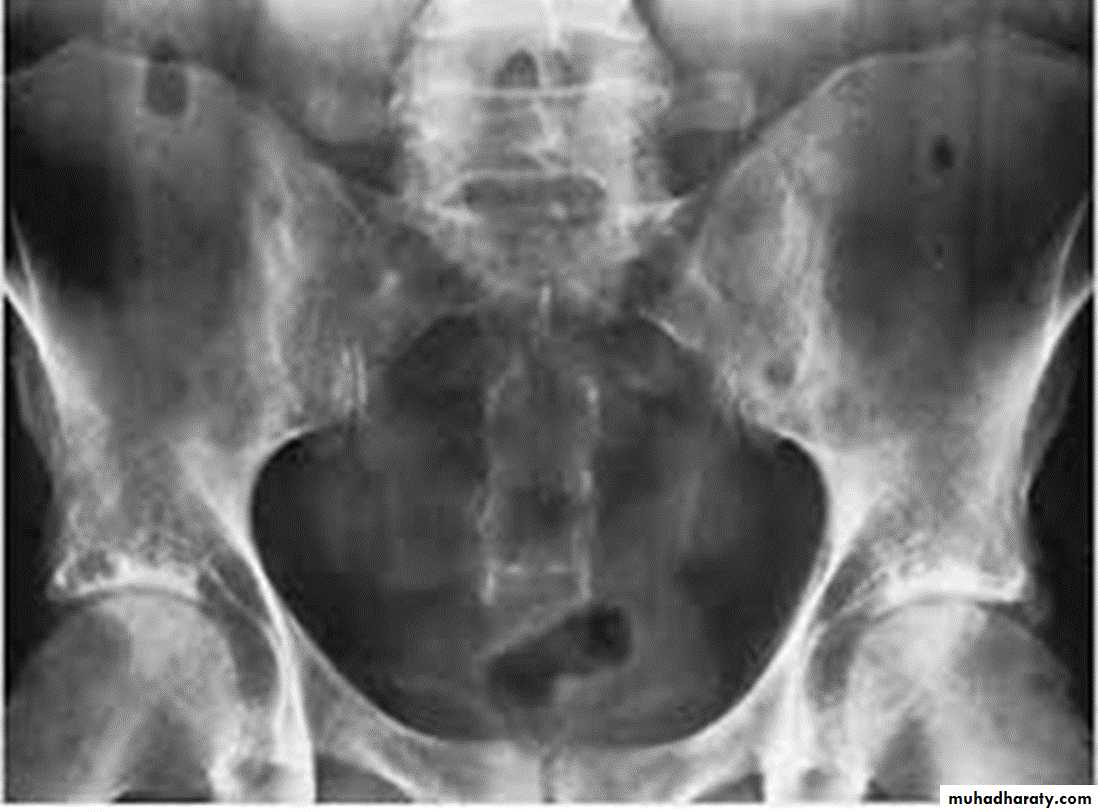

DEVELOPMENTAL DYSFLASIA OF HIP (CONGENITAL DISLOCATION OF THE HIP)

An abnormally lax joint capsule allows the femoral head to fall out of the acetabulum, leading to deformation.

CDH occurs most commonly (70%) in the left hip. Bilateral involvement is seen in 5%.

Radiographic features:

US (commonly used today) at 1-3 months

* Normal femoral head is covered at least 50% by acetabulum , In CDH < 50% of femoral head is covered by acetabulum .

Plain film

At 3-6 months :

By doing special veiw (Von Rosen veiw )by abduction of the thigh 45 degree and internal rotation .

In DDH the lines that drown through the femura will meet in higher level than the normally should at lumbosacral joint .

6 months and later

* AP veiw ( femural epiphysis are visualized ):* Superolateral displacement of proximal femur (disturbed shenton’s line )

* Increase in acetabular angle

* Small capital femoral epiphysis

Femoral head is located lateral to Perkin's line

* Other features that are sometimes present

Abnormal sclerosis of the acetabulum

Shallow acetabulum

Formation of a false acetabulurn